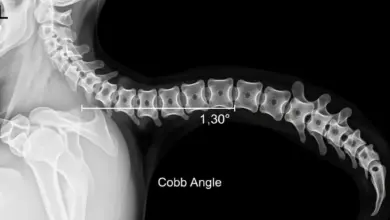

Exames de imagem não são obrigatórios para todos os pacientes.

Costumam ser mais úteis quando:

- A dor persiste apesar do tratamento inicial.

- Há sintomas neurológicos.

- Se suspeita de fratura, infecção, tumor.

- Existe planejamento de procedimento intervencionista ou cirurgia.